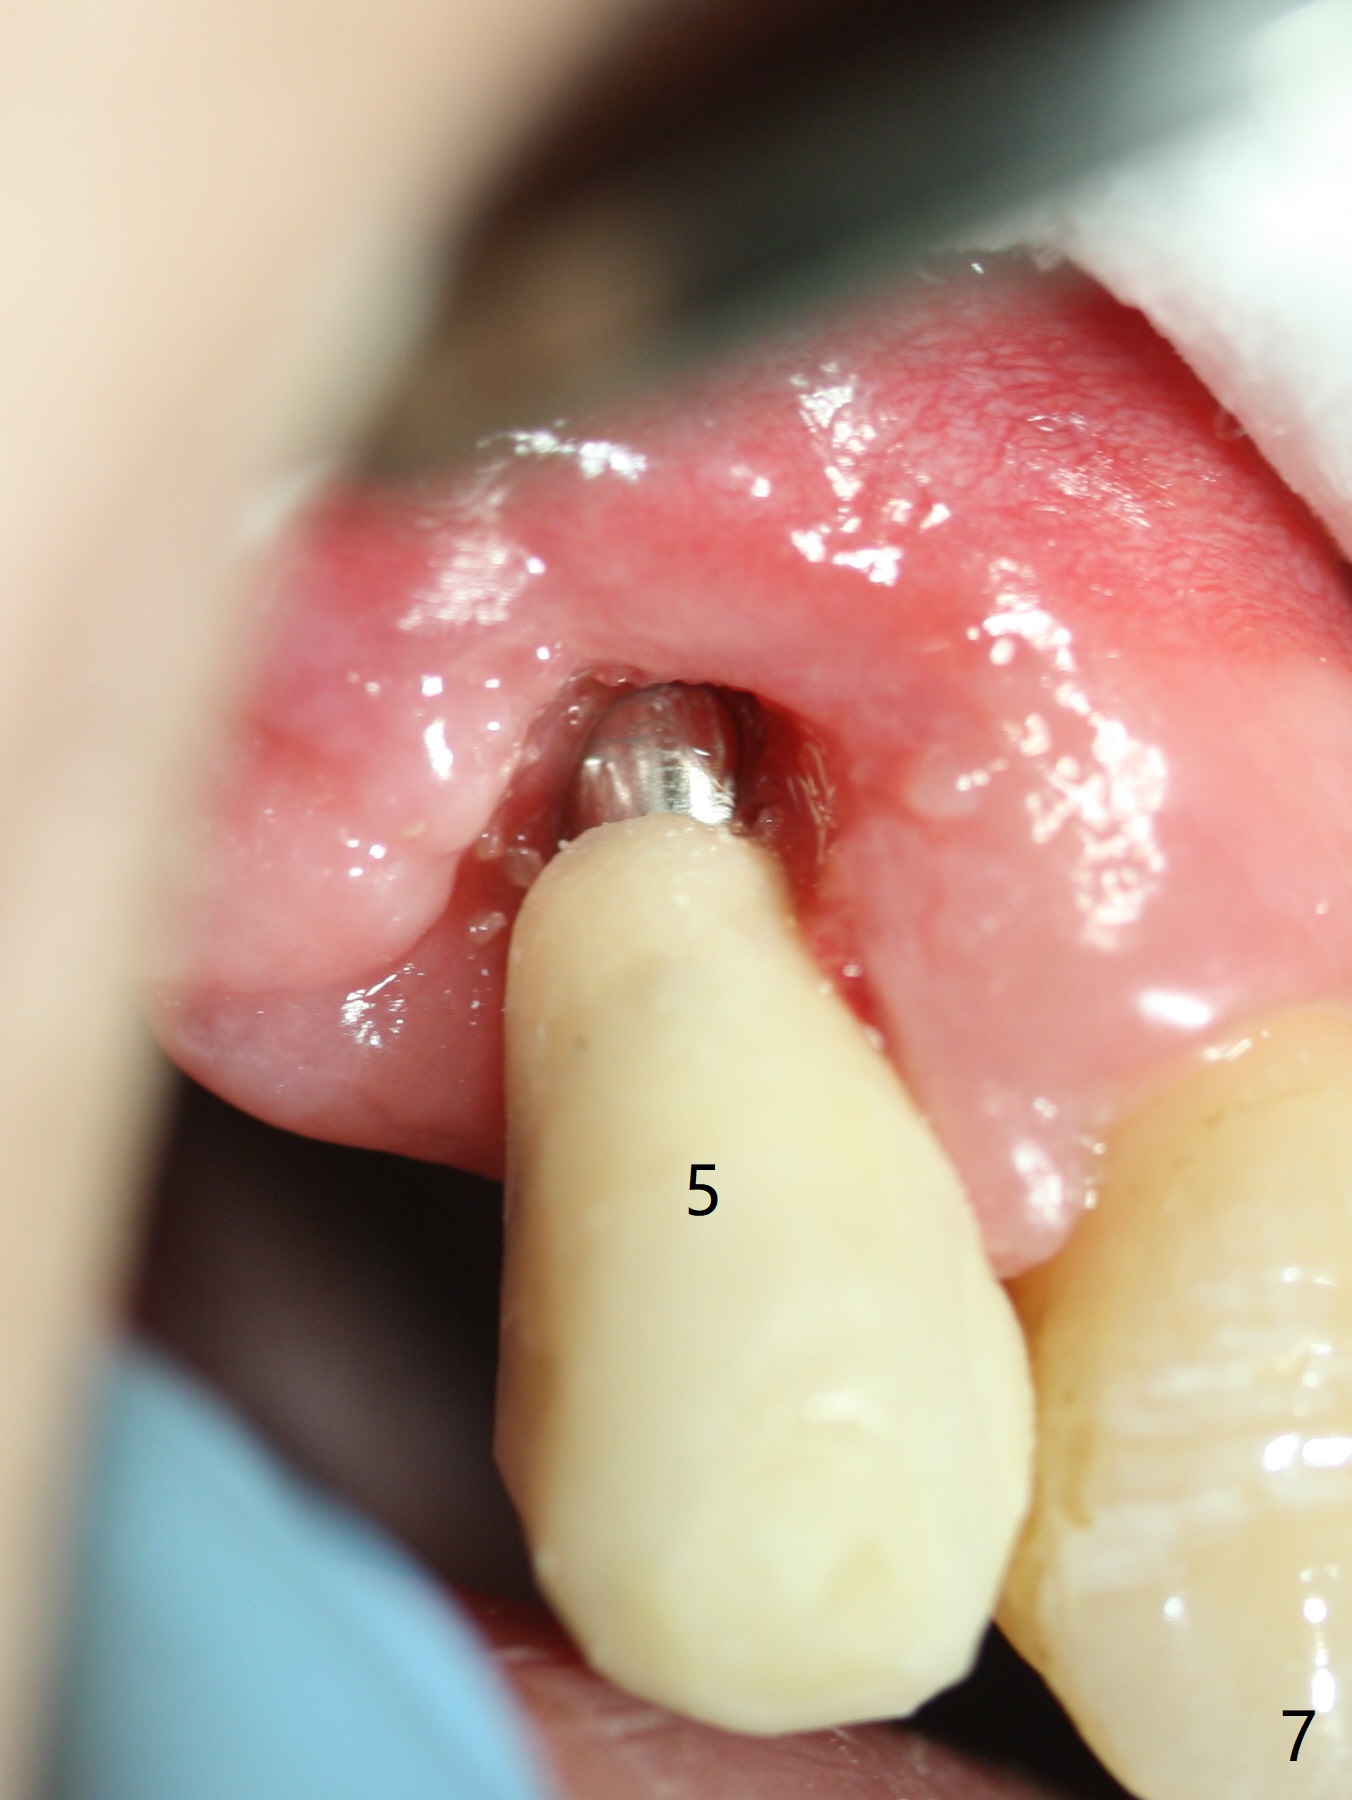

After extraction, the depths of initial osteotomy at #2, 3 and 5 are 13, 11.5 and 10 mm, respectively (Fig.1). Following adjustment of trajectory, a 3.8x13 mm UF implant is placed at #5 (Fig.2) with insertion of a 4.5x2 mm mill abutment as well as mineralized cortical/cancellous allograft (Vanilla, *). The mill abutment is chosen because the margin of a 5.5x7(5) mm cemented abutment is severely subgingival (Fig.4 at #3; ^ gingival margin). By the same token, a 4.5x3 mm mill abutment is placed at #2. In fact all of the 3 implants are placed 2-3 mm out of the bone (Fig.5). To prevent periimplantitis, abundant allograft is placed around the implants/abutments (Fig.2,4 *). Nearly 2 months postop, the mill abutment at #2 is adjusted for its height, while a 5.5x2.5 mm mill abutment is placed at #3 (Fig.6). To regain the buccal gingiva, the buccal margin of the provisional is shortened (Fig.6,7). Two weeks later, the gingival regrowth is not obvious (Fig.8 (nearly 3 months postop)). Local poor oral hygiene remains. A provisional FPD is fabricated. If his occlusion is normal for another 2 weeks, impression will be taken for upper (or UL) permanent restoration.